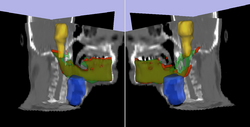

Initial experiments show that bony structures such as the mandible can be segmented accurately with a variational active contour. However, for soft tissue such as the brain stem, the intensity profile does not contain sufficient information for reasonably accurate segmentation. To deal with "soft boundaries" infinite dimensional active contours must be constrained by using shape priors and/or interactive user input. One way to constrain a segmentation is shown in our work in MTNS; there, known spatial relationships between structures is exploited. First, a structure we are confident in will be segmented. Using probabilistic PCA a metric used to describe how likely the structure whose segmentation we have obtained is; this metric is essentially a description of how confident we are in the correct segmentation. Then, the location of this structure will be used as prior information(it becomes a landmark) to segment a more difficult structure. Iteratively, the nth structure to be segmented will have n-1 priors do draw information from with a confidence metric for each prior. The likely location of the nth structure, calculated as described above, will serve as an input to constrain an active contours algorithm. Additionally, we have had excellent results when constraining structures of the eye to simple geometrical shapes such as ellipses and tubular to limit the number of free parameter. A sample segmentation of the eye ball is shown below.

• Rel Pred Prediction of mandible location(red) give a brainstem(yellow) and larynx(blue) segmentation; ground truth segmenation is green.

• Eye Seg Segmentation of the eye ball.